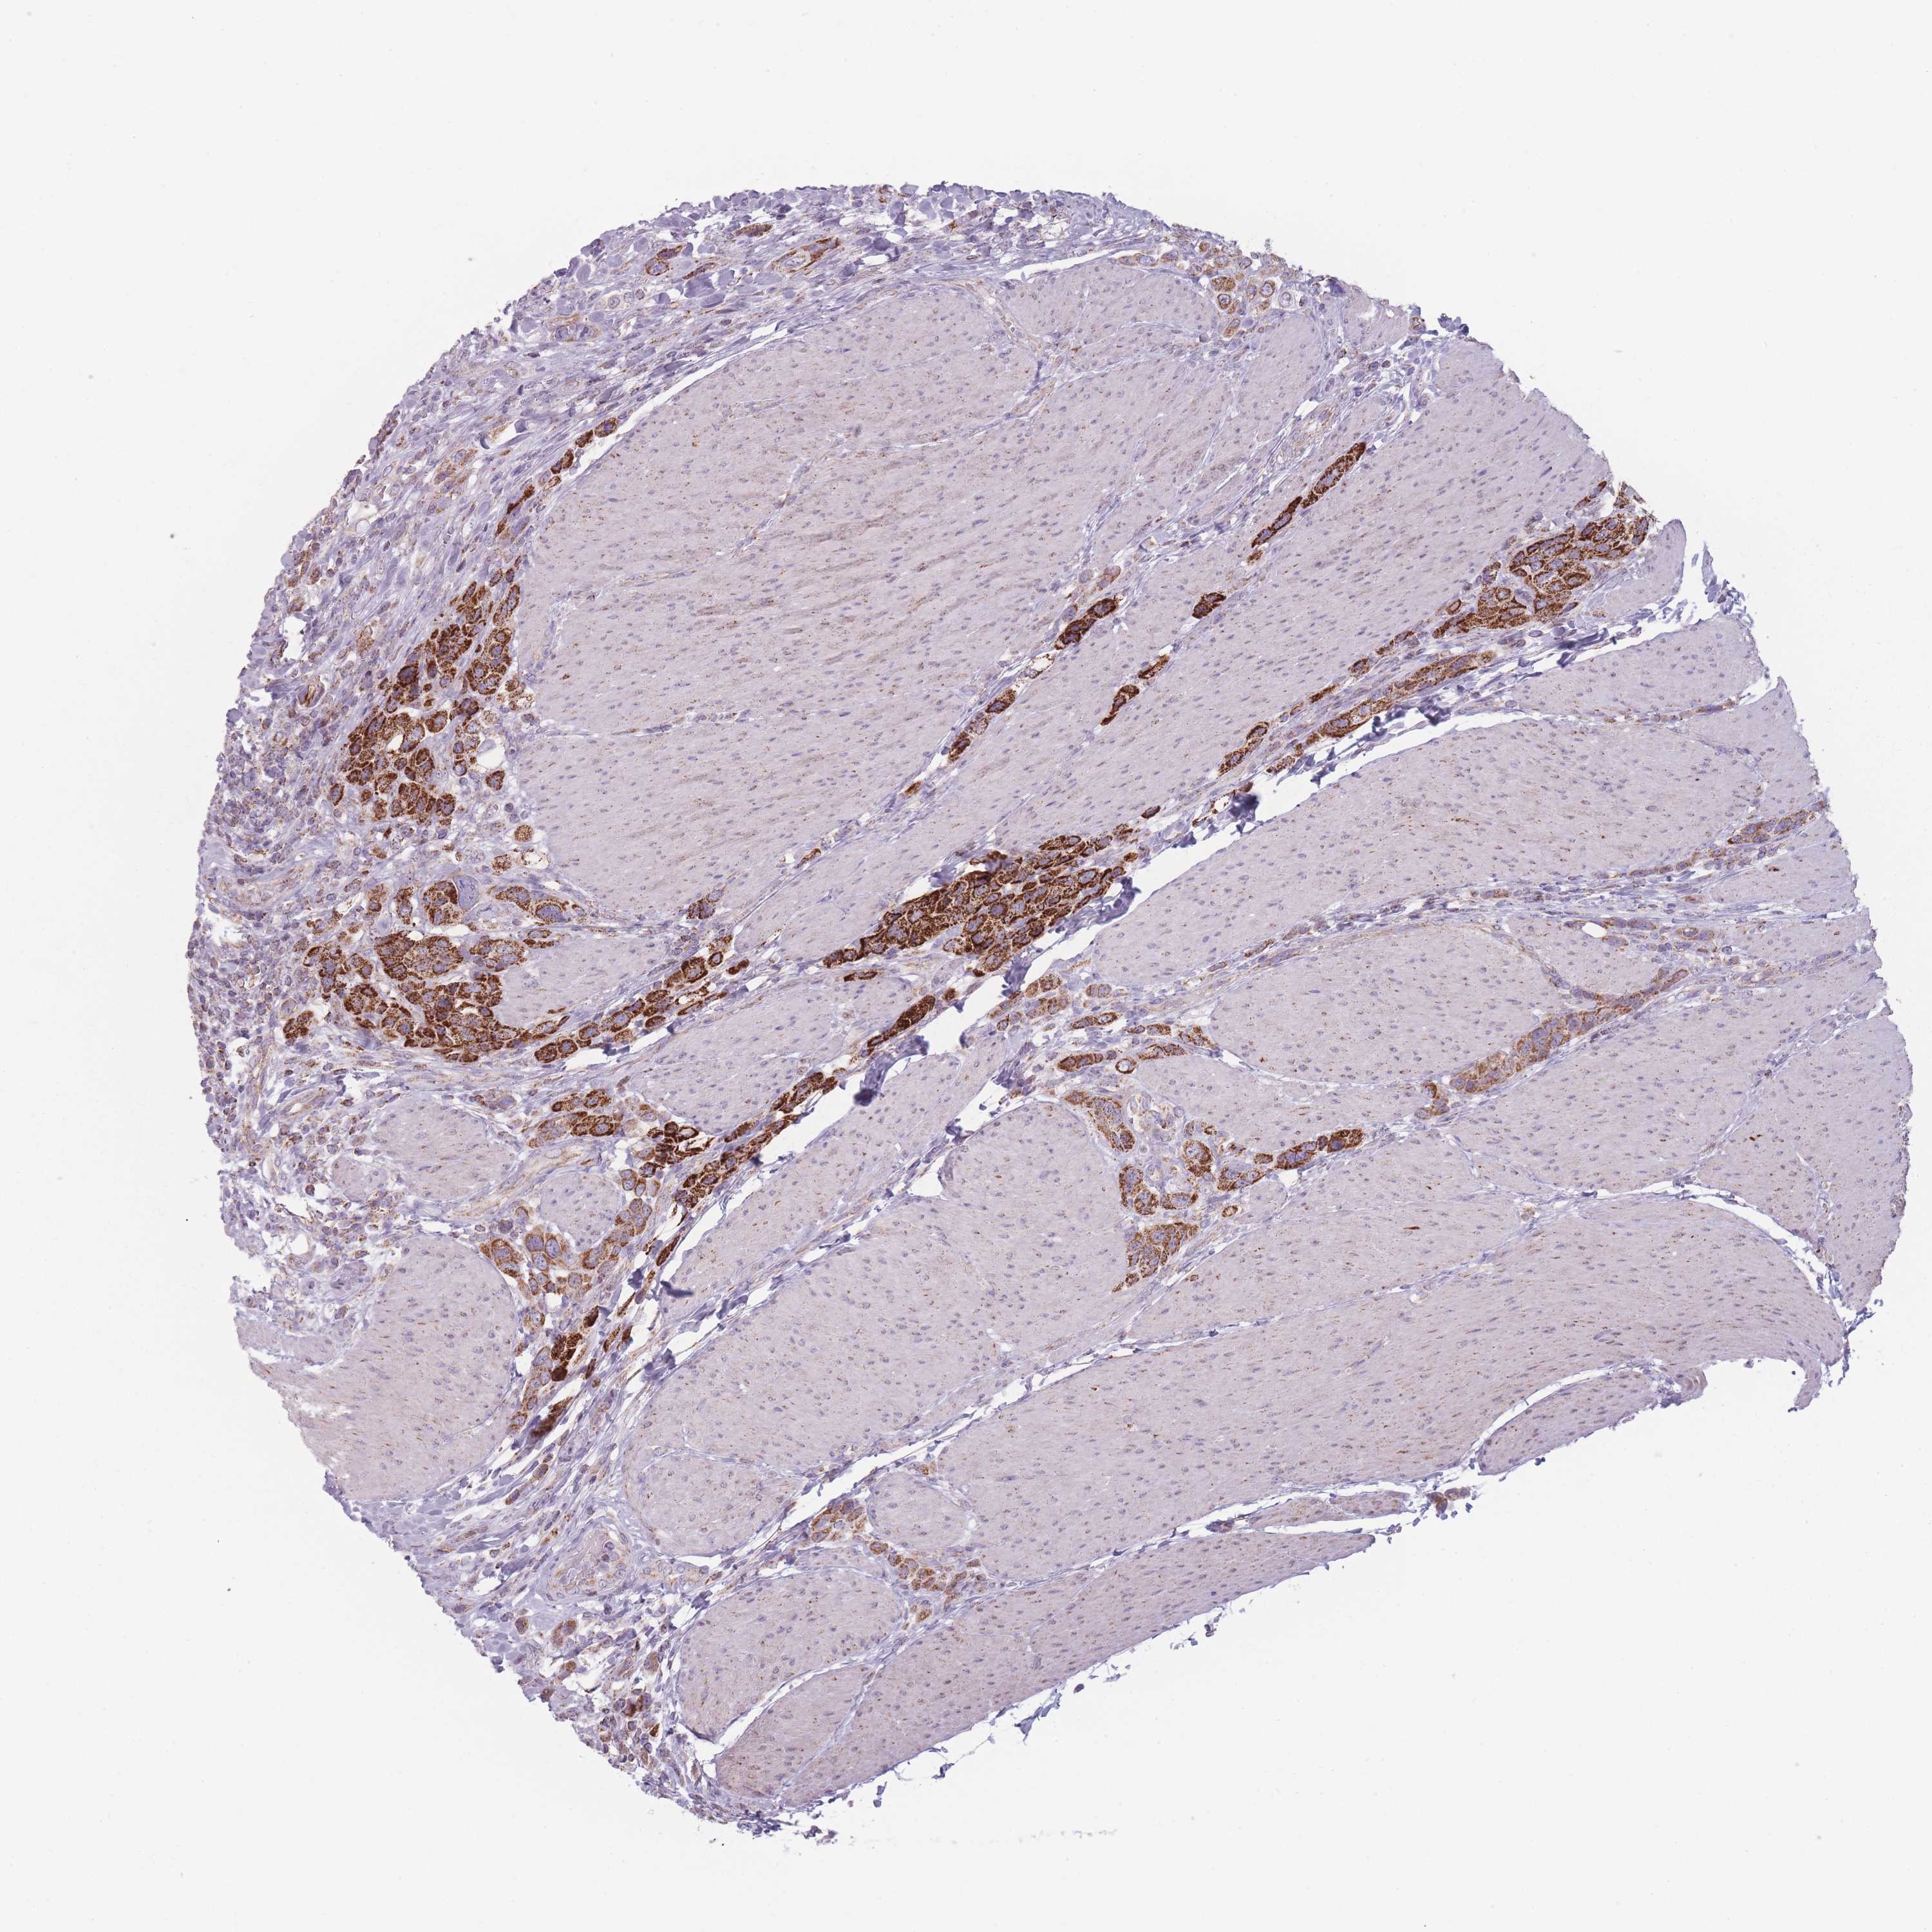

UROTHELIAL CANCER - Protein expressioni

A mouse-over function shows sample information and annotation data. Click on an image to view it in a full screen mode. Samples can be filtered based on level of antibody staining by selecting one or several of the following categories: high, medium, low and not detected. The assay and annotation is described here.

Note that samples used for immunohistochemistry by the Human Protein Atlas do not correspond to samples in the TCGA dataset.

Antibody stainingi

Antibody staining in the annotated cell types in the current human tissue is reported as not detected, low, medium, or high, based on conventional immunohistochemistry profiling in selected tissues. This score is based on the combination of the staining intensity and fraction of stained cells.

Each image is clickable and will lead to virtual microscopy that enables deeper exploration of all samples and also displays staining intensity scores, fraction scores and subcellular localization as well as patient and tissue information for each sample.

Antibody HPA017970

Antibody HPA050246

Staining

High

Medium

Low

Not detected

Intensity

Strong

Moderate

Weak

Negative

Quantity

>75%

75%-25%

<25%

None

Location

Nuclear

Cytoplasmic/membranous

Cytoplasmic/membranous,nuclear

Urothelial carcinoma, Low grade

Urothelial carcinoma, High grade

Urothelial carcinoma, NOS